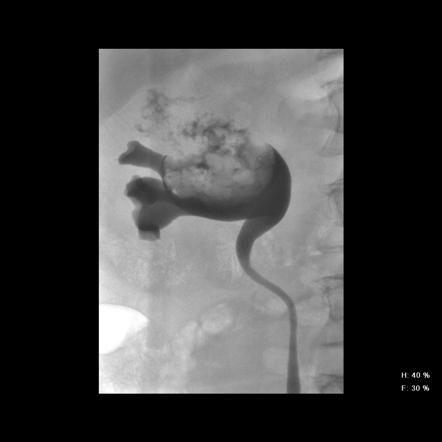

相关图片